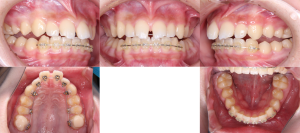

※矯正治療開始時

治療を進めやすくするために、噛み合わせを一時的に少し高くした状態で矯正治療を開始しました。

上の歯には装置が目立ちにくい舌側(内側)に、下の歯には一般的な唇側(外側)に装置を装着する、いわゆるハーフリンガル矯正を行いました。

この方法は、矯正治療中に装置の見た目が気になる方に配慮した治療方法の一つです。

※矯正治療開始時の上顎咬合面

装置を上の歯の内側(口蓋側)に装着することで、正面から見た際に装置が目立ちにくい状態となります。